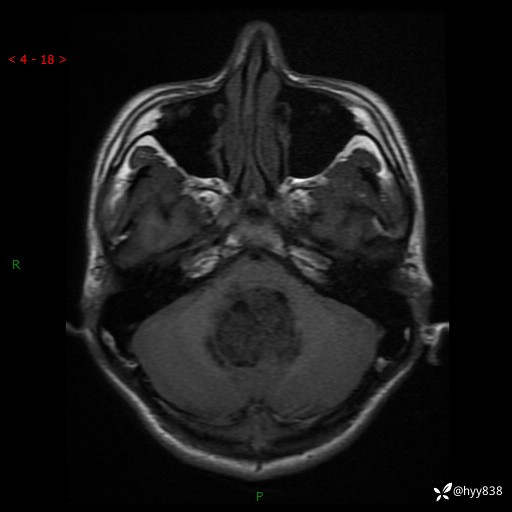

性别:男

年龄:17岁

简要病史:头痛伴间断性呕吐1月余,外院CT提示颅脑占位

颅脑MRI平扫+增强